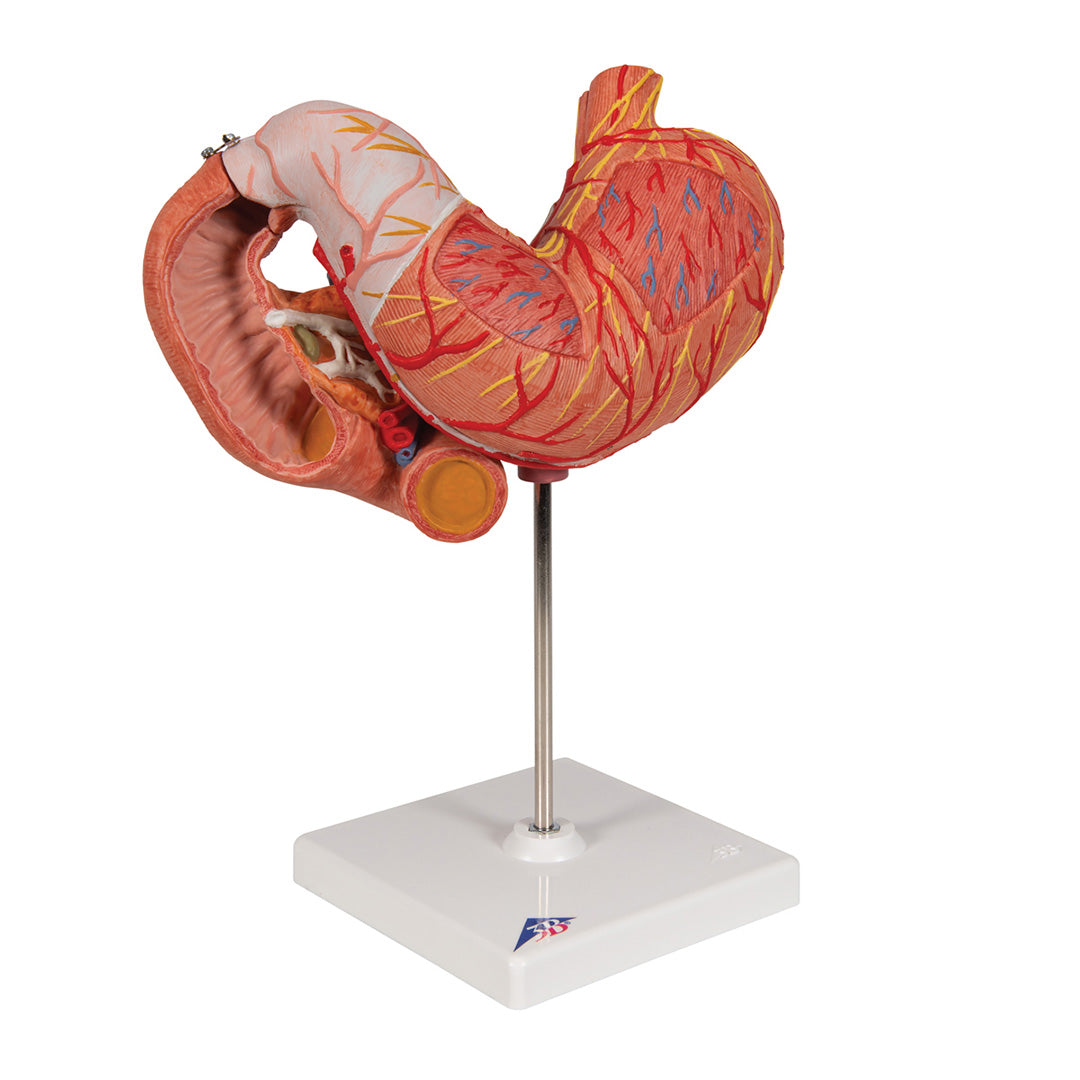

Estómago, en 3 piezas

Estómago, en 3 piezas

El modelo presenta las capas de la pared del estómago desde la cardia hasta el píloro.

La mitad delantera del estómago se puede retirar.

Se presentan:

• Parte inferior del esófago

• Conductos

• Nervios

• Duodeno

• Páncreas

Con soporte.

Peso 0.87 kg.

Dimension 25 x 22 x 12 cm